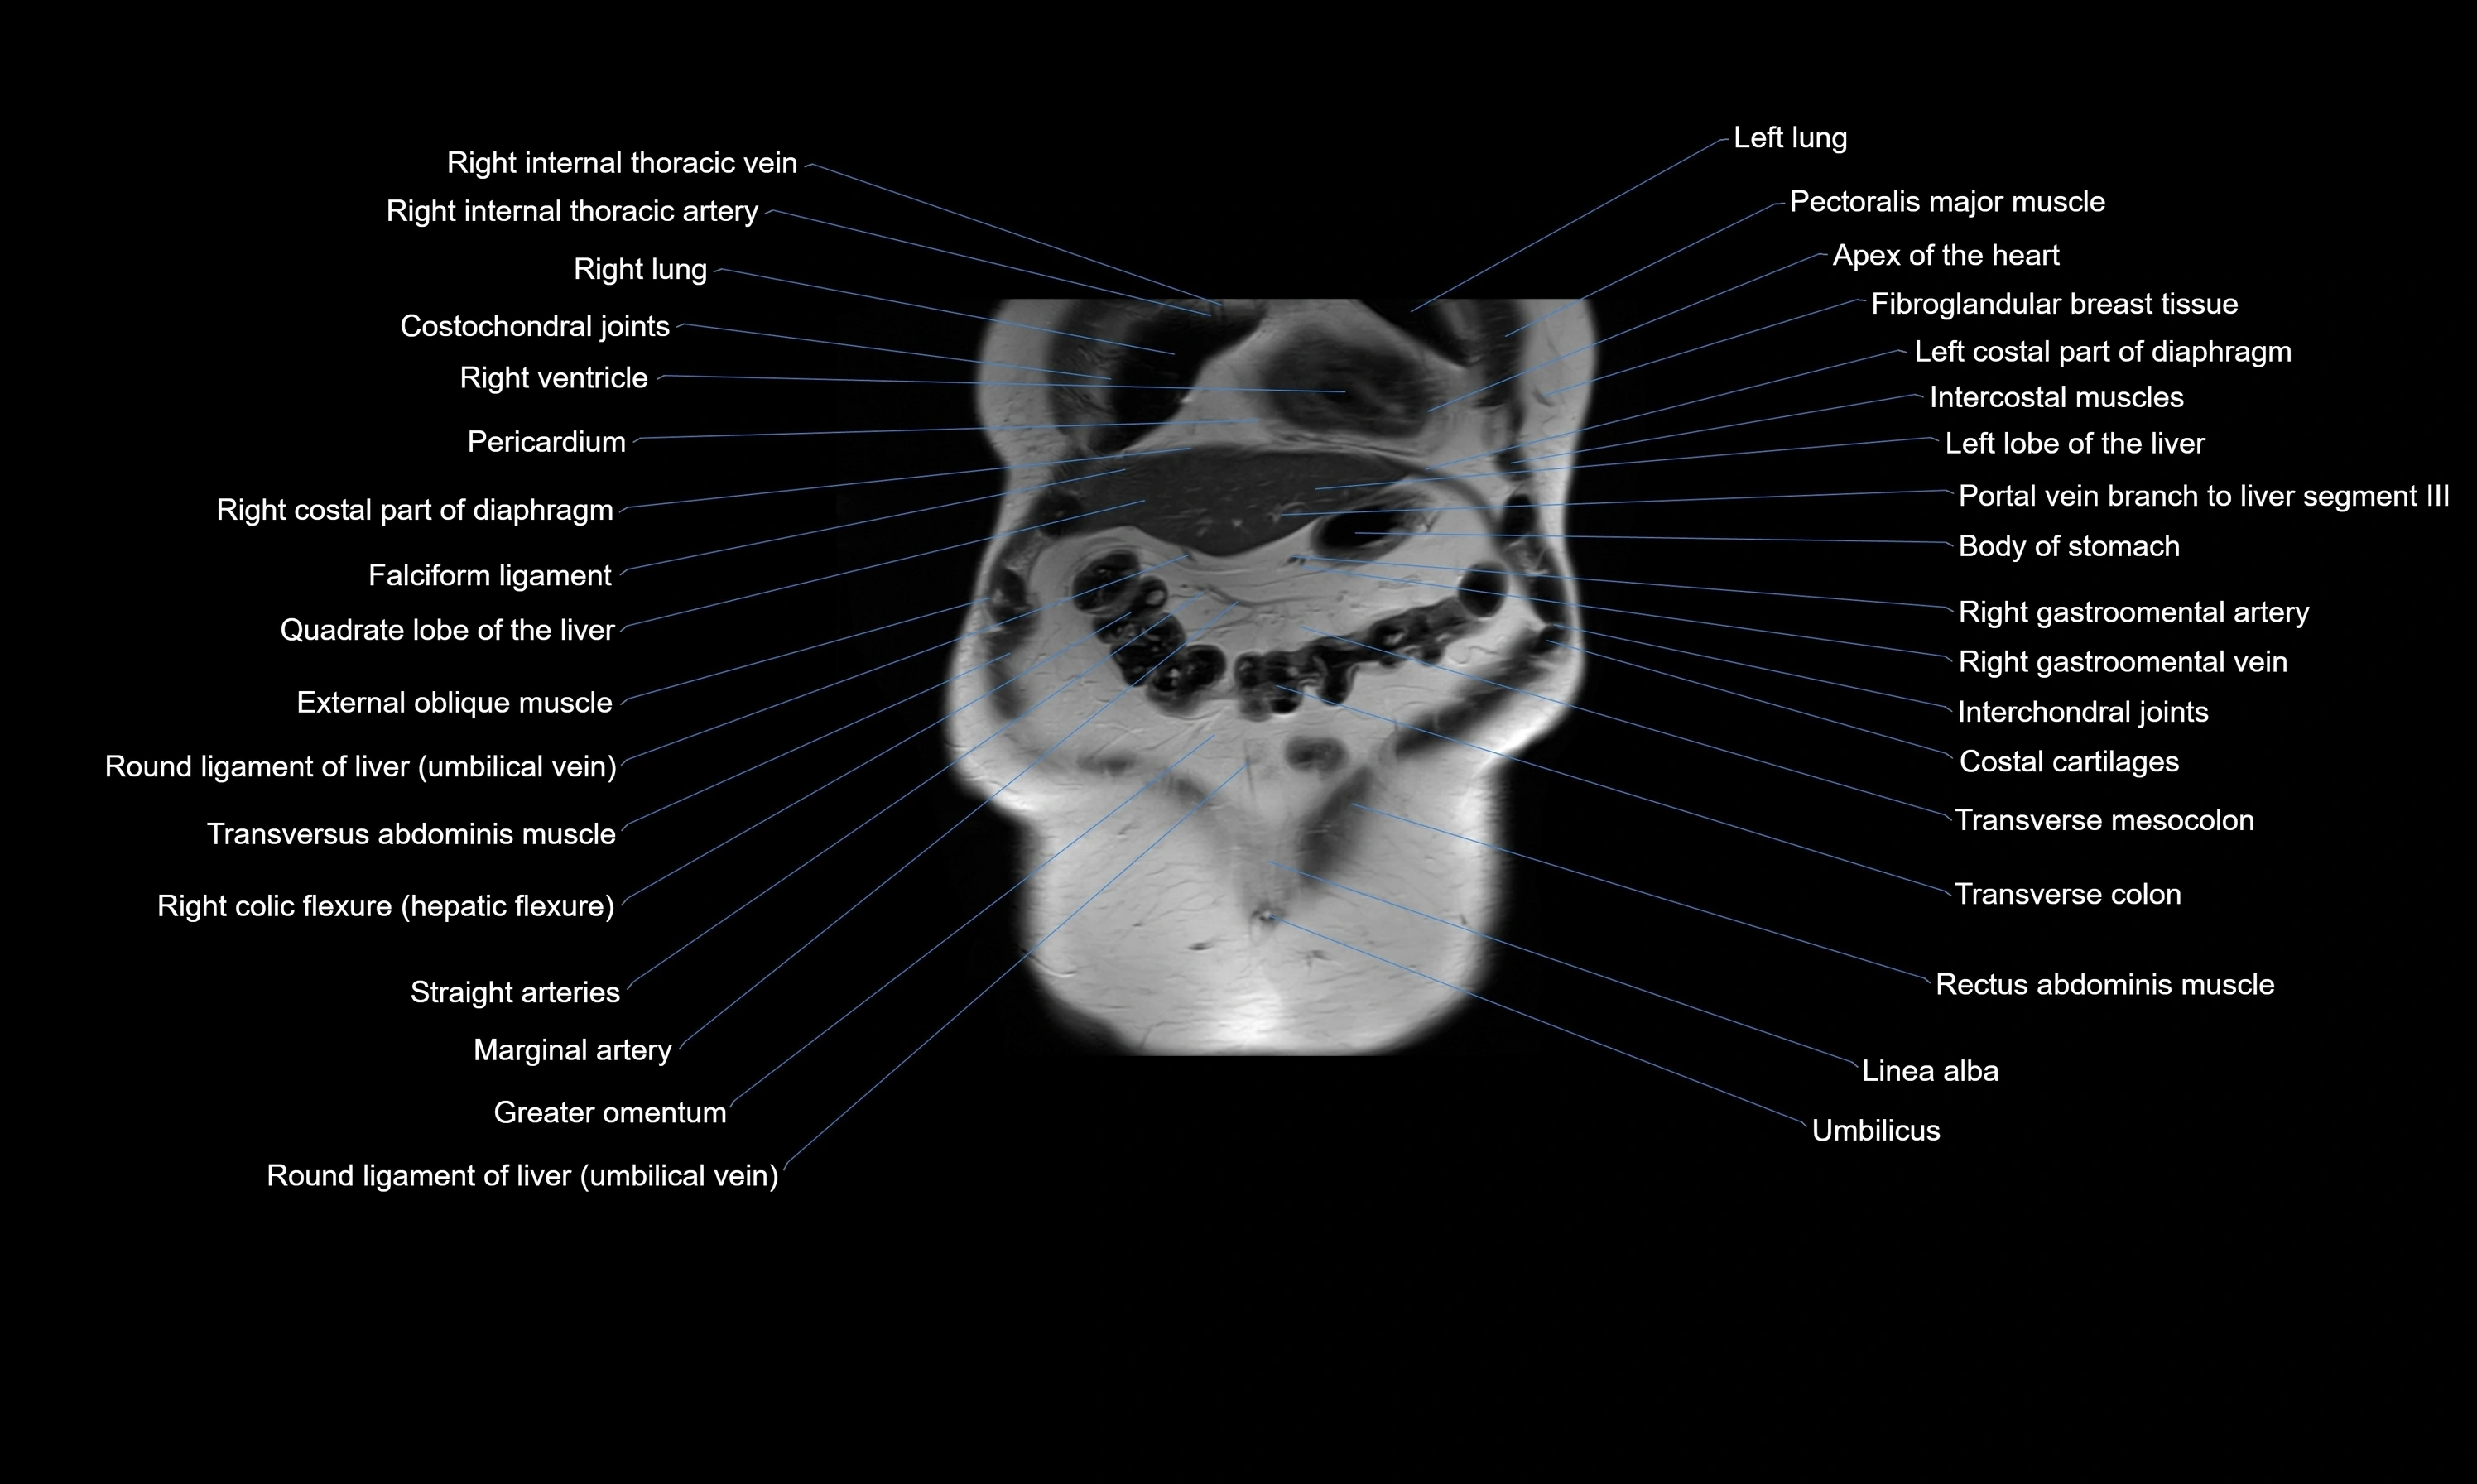

MRI images